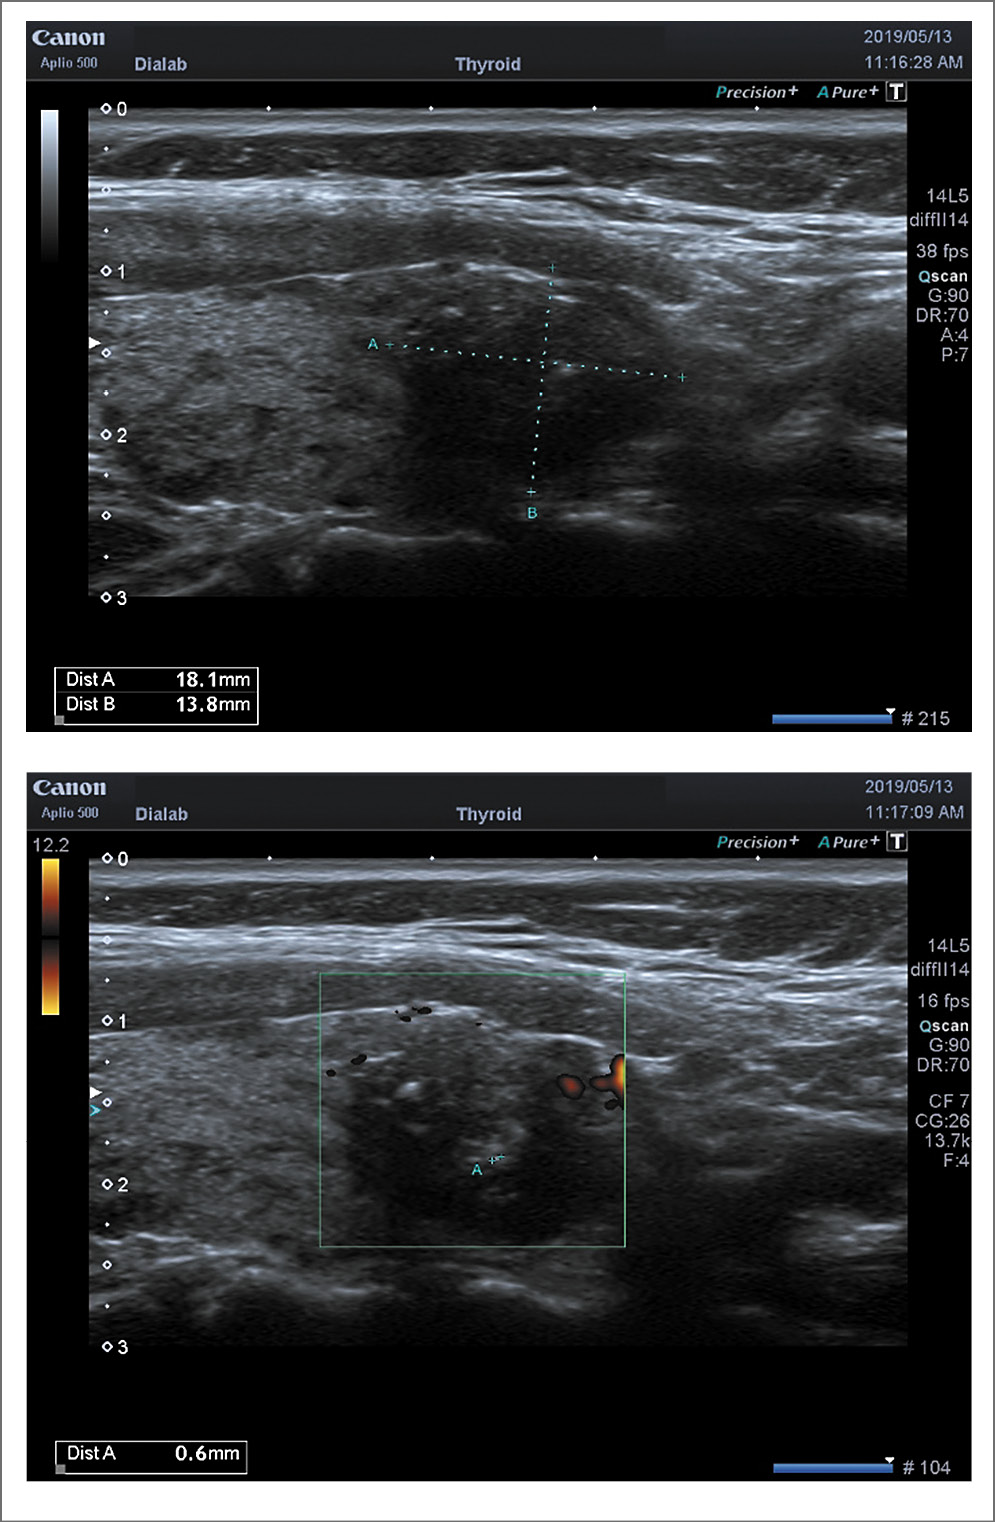

При определении риска злокачественности узлов ЩЖ по системе TI-RADS получены следующие данные: при ПР к категории 3 отнесены 13 (17,3%), 4а – 21 (28%), 4б – 31 (41,3%), 5 – 10 (13,4%) пациентов (рис. 1). При ПР на фоне АИТ в категорию 3 вошли 3 (15%), 4а – 7 (35%), 4б – 8 (40%), 5 – 2 (10%) больных (рис. 2).

Рис. 1. ПР, TI-RADS 4B (2D-режим). Небольшой узел с микрокальцификатами и преобладанием вертикального размера

Рис. 2. ПР на фоне АИТ, TI-RADS 4B (2D-режим). Изоэхогенный узел с неровными нечеткими контурами, микрокальцификатами, с единичным перинодулярным кровотоком.